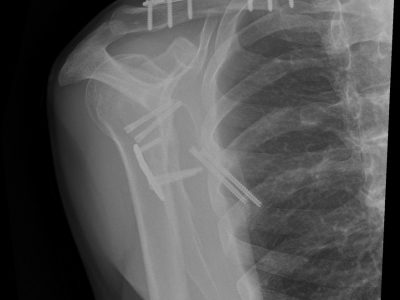

2. Αντιμετώπιση σύνθετων καταγμάτων βραχιονίου, ωμογλήνης, ωμοπλάτης και κλείδας.

Τα χειρουργεία πραγματοποιούνται αρθροσκοπικά ή με τεχνικές και τομές ελάχιστης επεμβατικότητας με γνώμονα τη ταχύτερη και βέλτιστη αποκατάσταση.

Παρακάτω παρατίθενται ακτινογραφίες καταγμάτων του άνω άκρου που αντιμετωπίζονται με εσωτερική οστεοσύνθεση ή επανορθωτική χειρουργική με αρθροπλαστική.